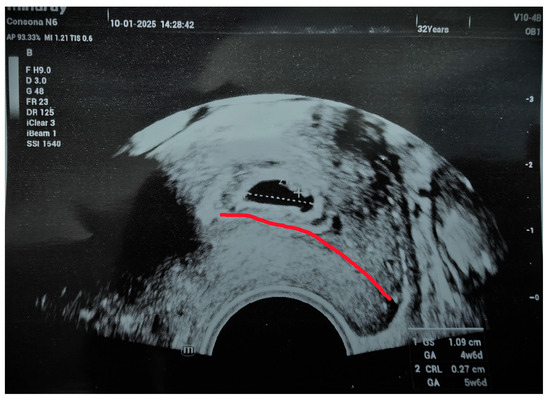

A follow-up scan confirmed a cervical pregnancy with a visible heartbeat and a crown-rump length (CRL) of 2.7 mm, consistent with a gestation of 5 weeks and 6 days (Figure 2). The patient had no major symptoms, was stable, and reported only light brown spotting. Blood tests were normal, and her β-hCG level was 5119 mIU/mL.

Figure 2. Vital cervical pregnancy (with the red line is marked cervical canal).